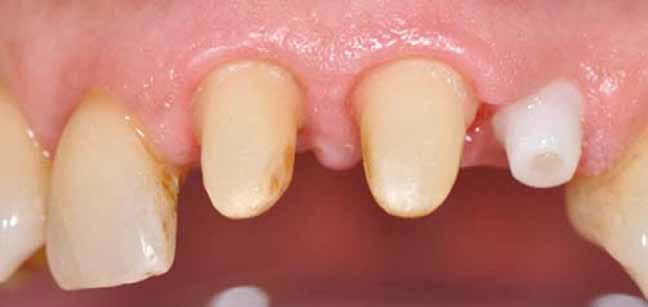

3. ábra: Intraorális helyzet a műtét előtt.

4. ábra: Felkészülés az implantátum behelyezésére.

5–6. ábra: A pótlás átadása után közvetlenül.